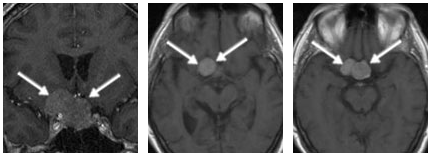

本例患者术前磁共振清晰显示,一个大型垂体瘤不仅向上生长压迫视交叉,更向侧方“攻城略地”,侵犯了右侧海绵窦。...